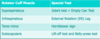

List the 4 rotator cuff muscles, their function and their tests of function?

Supraspinatus- abduction

Infraspinatus and teres minor- externally rotates the arm

subscapularis- internally rotates the arm

perform Jobe’s test